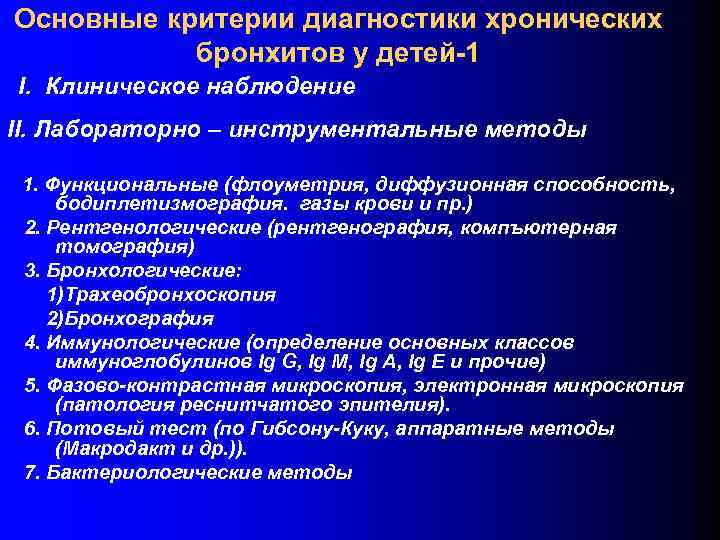

Основные критерии диагностики хронических бронхитов у детей-1 I. Клиническое наблюдение II. Лабораторно – инструментальные методы 1. Функциональные (флоуметрия, диффузионная способность, бодиплетизмография. газы крови и пр. ) 2. Рентгенологические (рентгенография, компъютерная томография) 3. Бронхологические: 1)Трахеобронхоскопия 2)Бронхография 4. Иммунологические (определение основных классов иммуноглобулинов Ig G, Ig M, Ig A, Ig E и прочие) 5. Фазово-контрастная микроскопия, электронная микроскопия (патология реснитчатого эпителия). 6. Потовый тест (по Гибсону-Куку, аппаратные методы (Макродакт и др. )). 7. Бактериологические методы